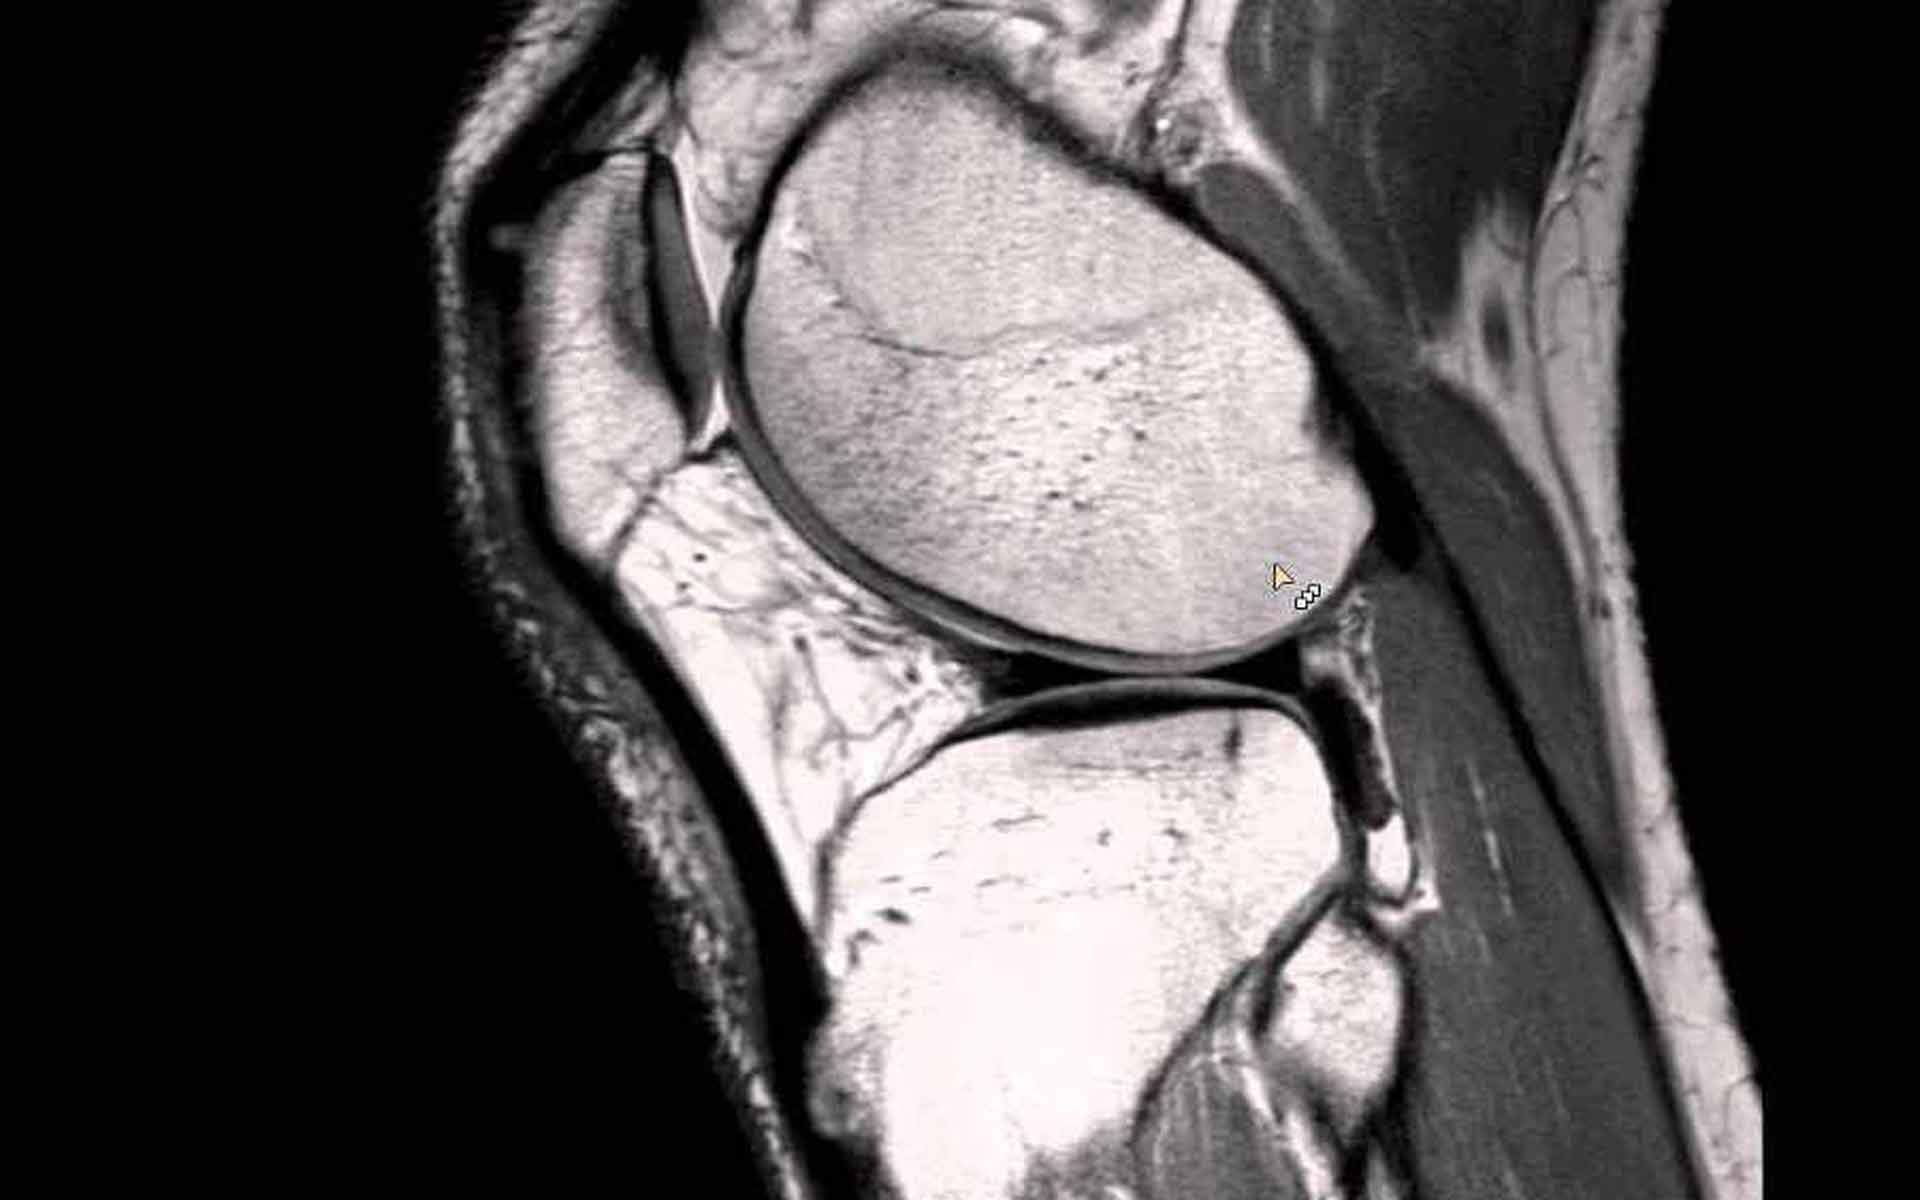

Habrá sensibilidad a lo largo de la articulación en el interior de la rodilla y es probable que el rango de movilidad se vea restringido. Un profesional clínico puede confirmar el diagnóstico con la ayuda valoraciones específicas, que incluyen los test de McMurray y Apley, y puede referir una resonancia magnética para confirmar el alcance de la lesión.

3. Evaluación Especializada: Si el dolor y la hinchazón persisten, podría ser necesario realizar una evaluación más profunda, como una resonancia magnética, para obtener una imagen más detallada de las estructuras de la rodilla. Esto podría ayudar a los médicos a comprender mejor la causa de tus síntomas y a ajustar el tratamiento en consecuencia.